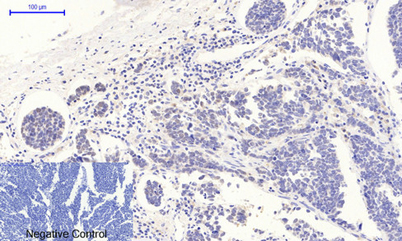

p53 (phospho Thr18) rabbit pAb

Product name: p53 (phospho Thr18) rabbit pAb

Dilutions: IF: 1:50-200 WB 1:500-2000, IHC 1:50-300 IHC 1:50-300

Immunogen: The antiserum was produced against synthesized peptide derived from human p53 around the phosphorylation site of Thr18. AA range:1-50